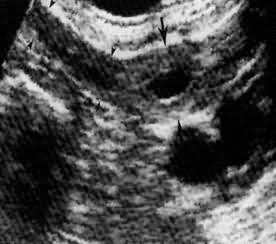

röntgende intrauterin yavru ultrasound köpekte 25 günlük gebelik